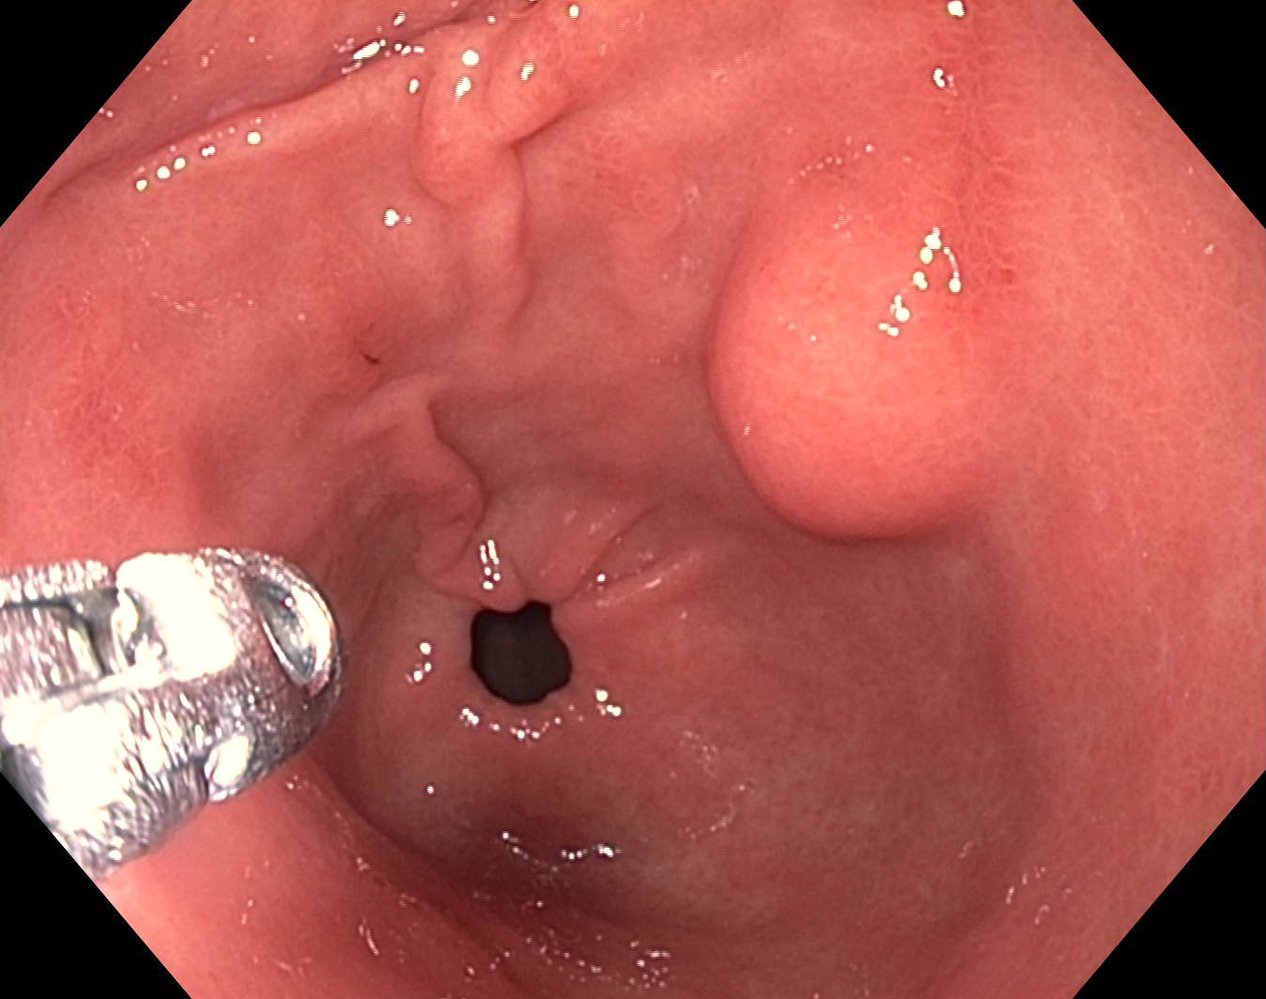

Gastric cancer

Endoscopy view of the gastric antrum

There is a gastric mass at the level of the lesser curvature with an irregular margin (perimeter marked by green outline) and central ulceration (green overlay).

These findings are consistent with gastric cancer.